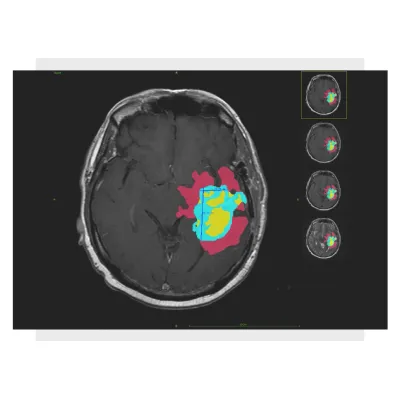

Graylight Imaging specializes in developing advanced AI technologies for medical image analysis, providing accurate, automatic, and customized software solutions. These solutions extract critical data from patient scans, addressing unique challenges in the medical field. Our team creates sophisticated algorithms that detect, outline, and analyze organs and abnormalities in MRI, CT, PET, and Angio-CT scans. Utilizing both traditional machine learning methods and advanced deep learning techniques, we ensure precision and efficiency in organ contouring, tumor segmentation, and cardiovascular imaging, among other applications. Our solutions streamline processes such as automatic segmentation and measurement, facilitating tasks like RANO and RECIST assessments. We maintain a strong track record in the industry, having ranked highly in competitions like the RSNA-ASNR-MICCAI Brain Tumor Segmentation Challenge. Additionally, our 3D modeling toolkit supports detailed analysis and fluid flow simulations, offering comprehensive capabilities for medical professionals.Accurate. Automatic. Advanced. Custom AI medical image analysis software solutions can provide you with data embedded in patient scans.

Tumors segmentation

Based on your requirements, we can design customized automated and semi-automated algorithms to analyze internal organs and lesions.

We create custom cutting-edge algorithms that streamline the segmentation process, allowing radiologists to focus on more complex tasks.

Algorithms accuracy and performance